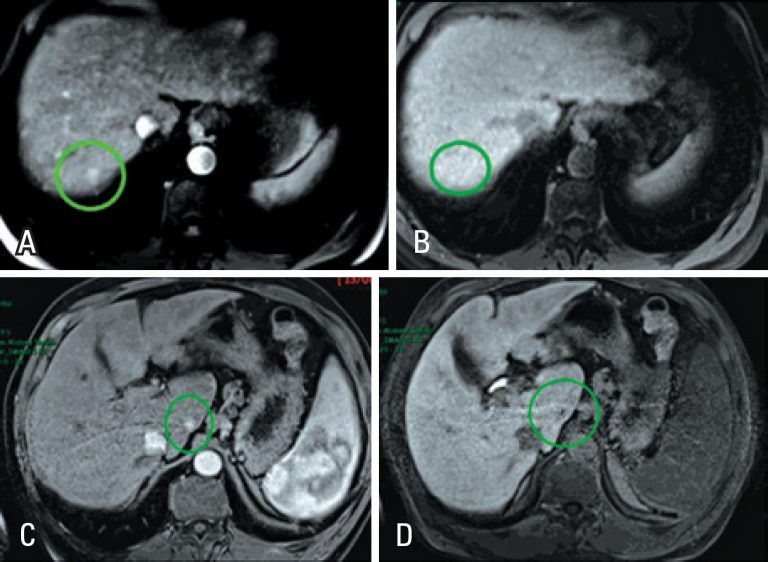

ABSTRACT The hepatobiliary-specific contrast medium (gadoxetic acid – Primovist®) is primarily used to improve detection and characterization of focal hepatic lesions, such as in chronic liver disease patients with suspected hepatocellular carcinoma. Since the contrast medium is selectively taken up by functioning hepatocytes in the late hepatobiliary phase, it helps to detect typical hepatocellular carcinoma, which show low signal intensity on this phase. This imaging feature also assists in differentiating regenerative/dysplastic nodules from early hepatocellular carcinomas (with over 90% accuracy), […]

Keywords: Carcinoma, hepatocellular/diagnosis; Contrast media/utilization; Liver diseases/diagnosis; Liver neoplasms/diagnosis; Magnetic resonance imaging/methods